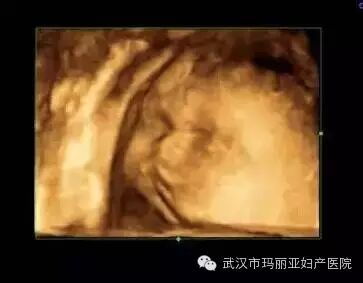

武汉玛丽亚妇产医院引进的世界领先的美国GE-E8四维彩超设备室目前世界上最先进、分辨率最高的彩色超声设备,具有即时立体成像、清晰准确的特点。

它能够多方位、多角度地观察宫内胎儿的生长发育情况,为早期诊断胎儿先天性体表畸形和发育异常提供科学依据。还能对胎儿的体表进行检查,如唇裂、脊柱裂、大脑、肾、 骨骼发育不良等,以便尽早的进行治疗。

玛丽亚美国GE-E8四维彩超排畸成功案例